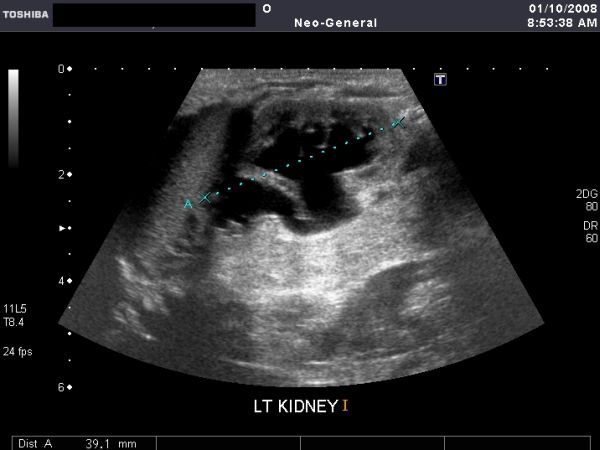

This young child shows an anechoic collection (of fluid) in the left pleural cavity. The left lung (lower lobe) shows echogenicity and texture similar to that of the liver (hepatisation). The spleen is seen below the left hemidiaphragm. These ultrasound images suggest left pulmonary consolidation with left pleural effusion. Images taken using a Toshiba Xario ultrasound machine, by Dr. Joe Antony, Cochin.